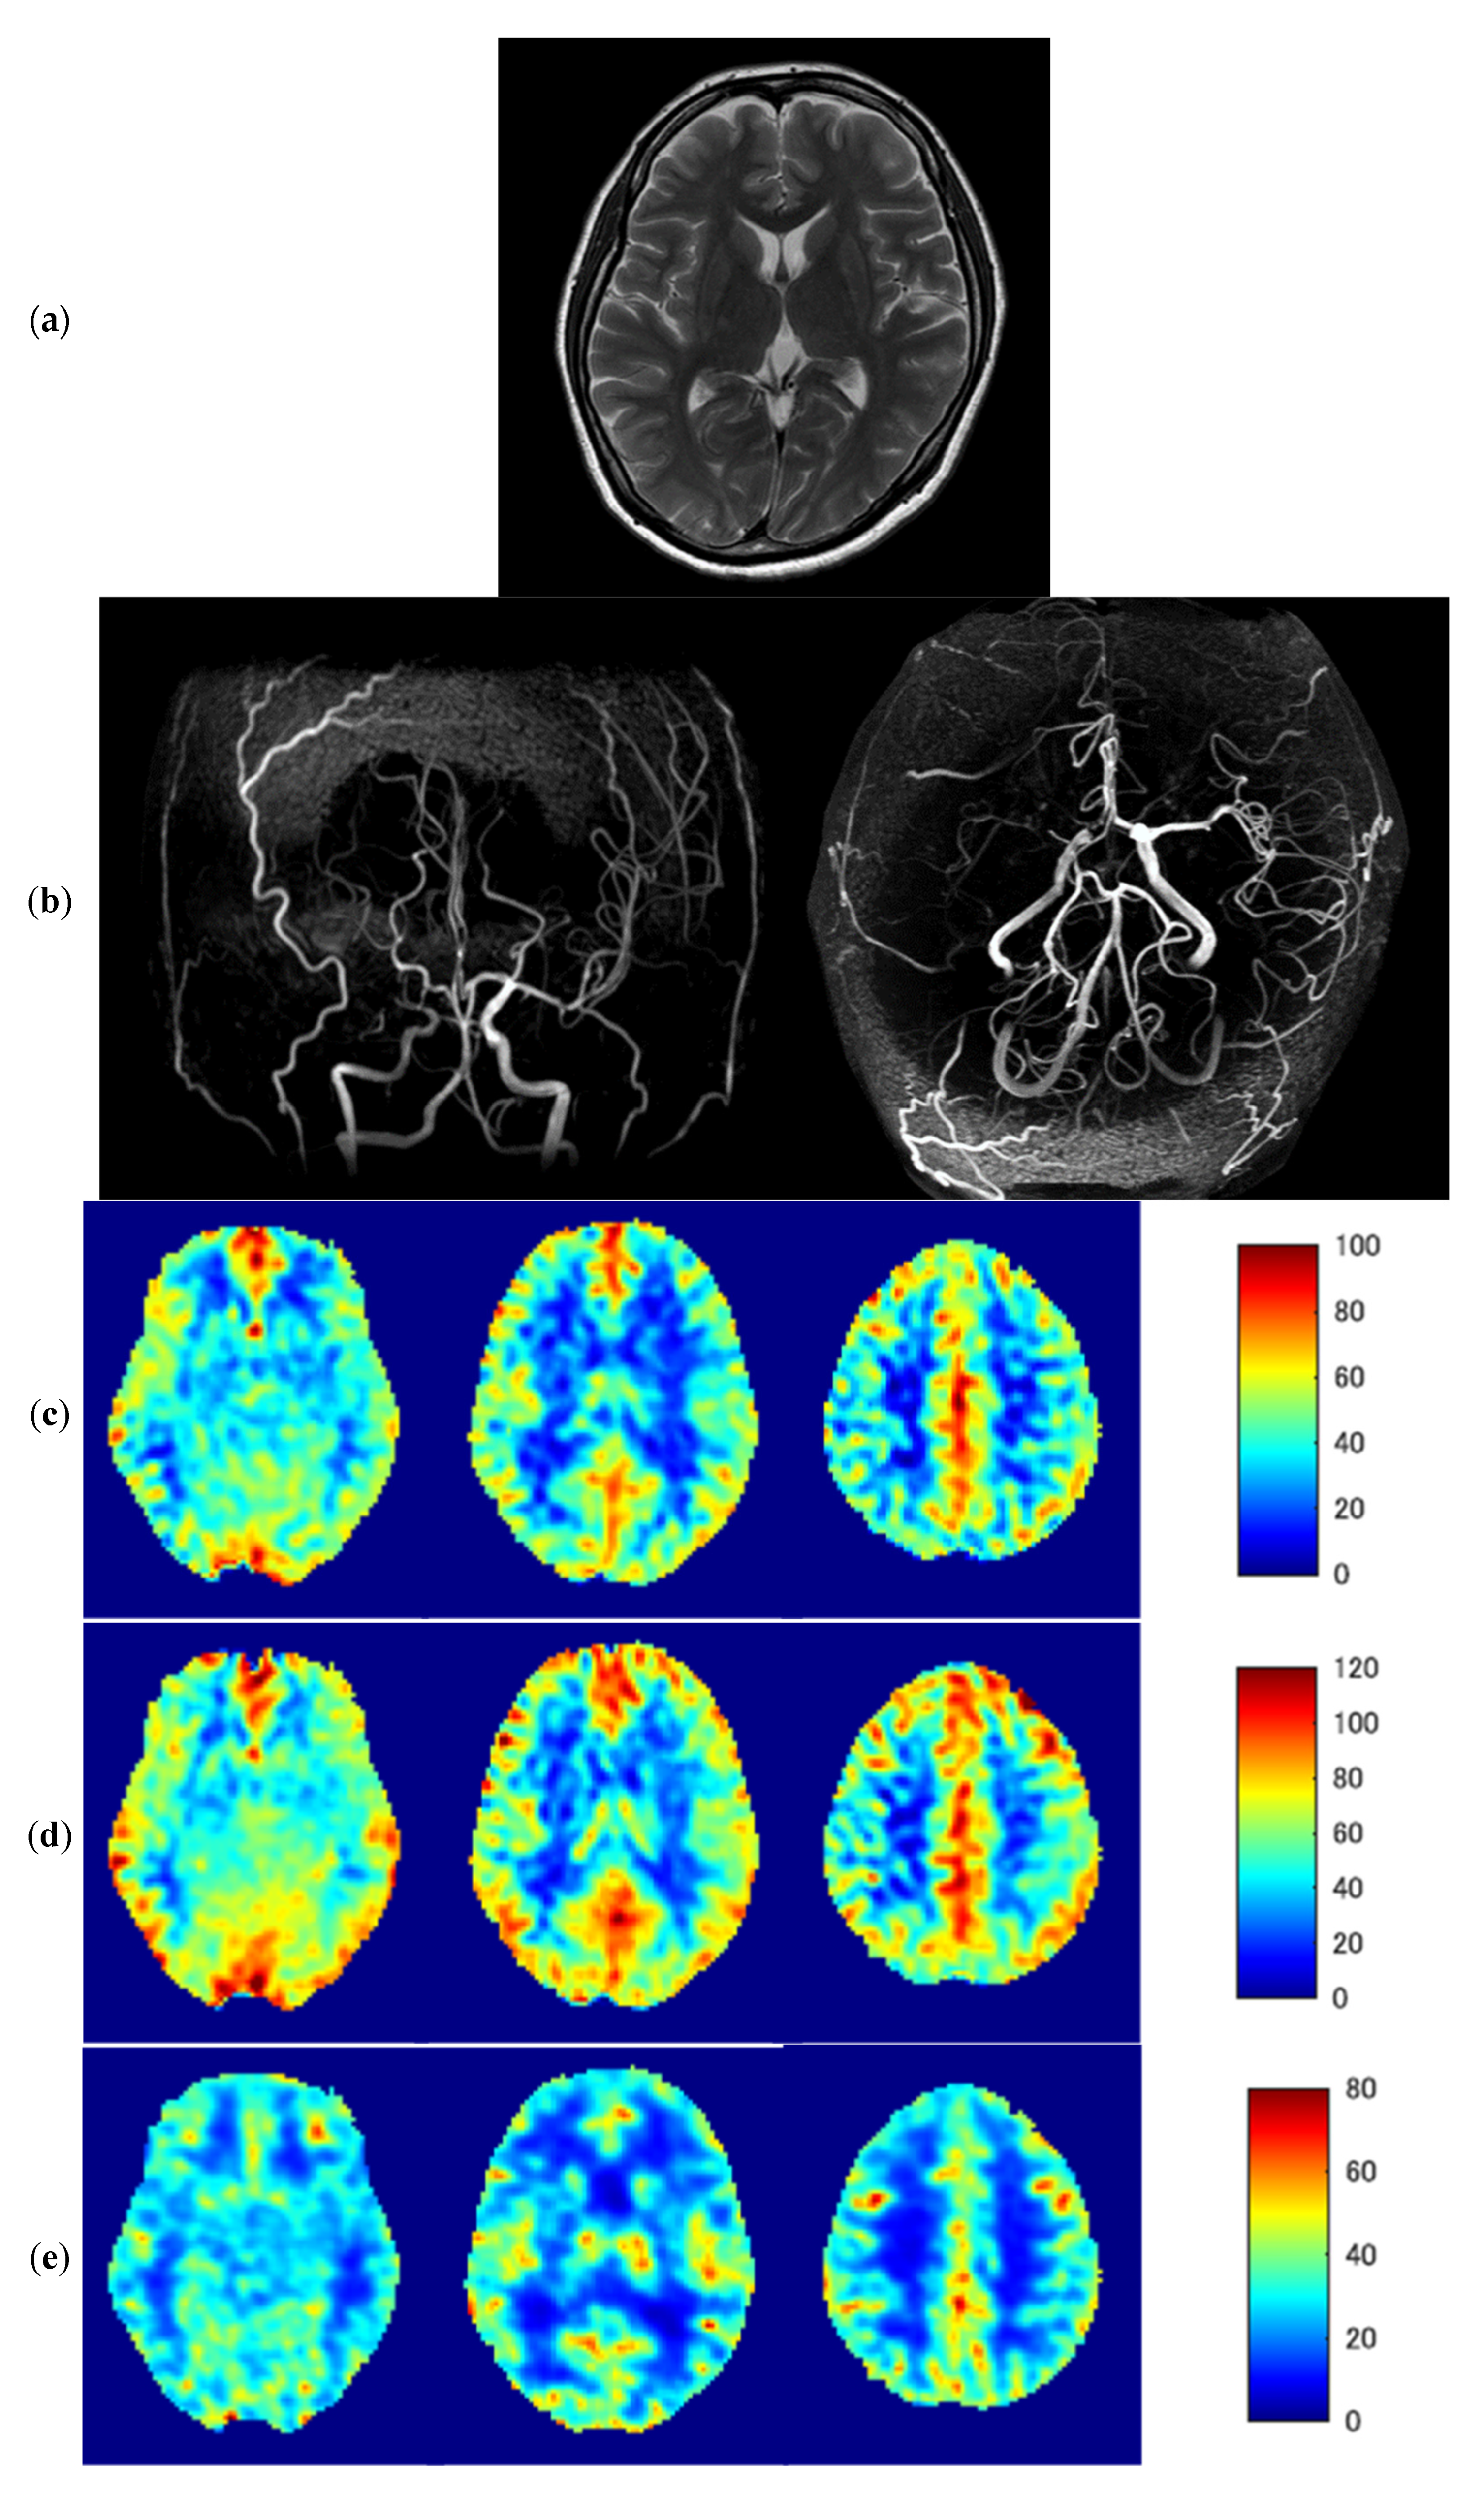

Once ATT was determined by the weighted delay method, CBF with ATT correction was calculated. The details how the ATT corrected CBF in the least-squares solution using all [LD, PLD] conditions is previously reported [19]. Figure 1 demonstrates the calculation of ATT corrected ASL-CBF from five perfusion signals, four from Hadamard and the other from LLLD acquisition, in a normal subject.

Figure 1.

The calculation of ATT corrected ASL-CBF using the combined Hadamard and long-labeled long-delay (LLLD) acquisitions. (a) Perfusion signal (ΔM/M0) map of [LD, PLD] = [1.33, 0.7], (b) ΔM/M0 map of [LD, PLD] = [1.33, 2.03], (c) ΔM/M0 map of [LD, PLD] = [1.33, 3.36], (d) ΔM/M0 map of [LD, PLD] = [4.0, 0.7], (e) ΔM/M0 map of [LD, PLD] = [4.0, 3.0], (f) ATT-corrected CBF, (g) ATT map, (h) plots of each ΔM/M0 and the draw of selected least square solution. Plotted points are in left cerebral cortical pixel in the central semiovale section of the maps of (a–e), respectively.

3.3. Representative Images

Figure 5 shows representative images of a 46-year-old woman with severe MMD (patient No. 6) with transient ischemic attack (TIA) symptoms. A T2-weighted MR image (a) shows no abnormal findings in the brain parenchyma; however, MR angiography (b) demonstrates severe stenosis of the right ICA. Despite the slight overestimation of ASL-CBF compared with PET-CBF, baseline and post-ACZ ASL-CBF with ATT correction (c,d) are similar to baseline and post-ACZ PET-CBF (e,f), respectively. Baseline ASL-ATT was prolonged in the right MCA territory (g). Although the prolonged ASL-ATT in the right MCA territory remained about the same even after ACZ loading, post-ACZ ASL-ATT was shortened in the left MCA territory due to the decreased vascular resistance (h). Decreases in ΔPET-CBF and PET-CVR in the right MCA territory (i,j, respectively) were similar to a negative/positive inversion of prolonged ASL-ATT.

Figure 5.

Representative images of a 46-year-old woman with severe Moyamoya disease (patient No. 6). T2-weighted MR image (a), MR angiography (b), baseline ASL-CBF (c), post-ACZ ASL-CBF (d), baseline PET-CBF (e), post-ACZ PET/CBF (f), baseline ASL-ATT (g), post-ACZ ASL-ATT (h), ΔPET-CBF (i), and CVR (j) CVR; cerebrovascular reactivity.